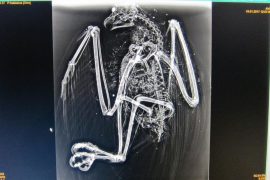

Troben una àguila peixetera tirotejada prop de l'Aeroport de Palma

Els vigilants de seguretat de l'aeroport han trobat prop de les instal·lacions aeroportuàries de Palma un exemplar...